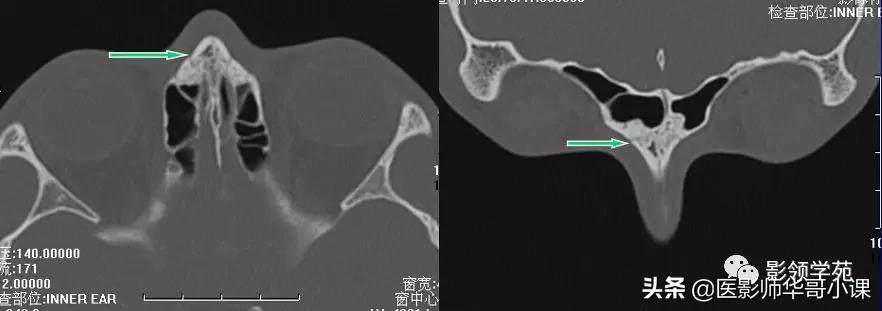

线性骨折 粉碎骨折

右侧鼻骨线形骨折

鼻骨线形骨折

左侧鼻骨线形骨折